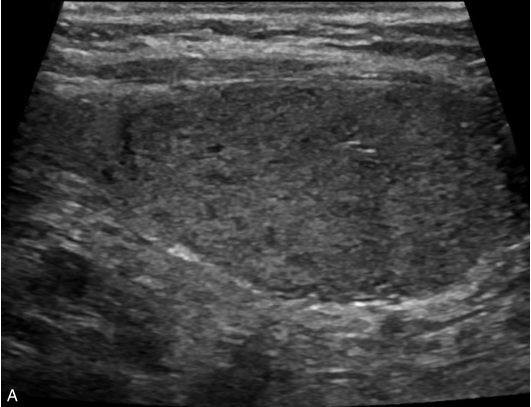

男性,52岁,外院发现甲状腺结节,为求进一步诊治收入我院。

甲状腺左叶中下部见一混合回声结节,边界清,形态规则,中心部可见斑状强回声,CDFI显示周边可见环状血流信号,其内可见丰富血流信号,见图1-3-18。

该结节早于周围腺体组织增强,结节内部呈高增强表现,可见部分无增强区;结节晚于周围腺体组织消退,仍呈高增强表现;结节周边可见均匀高增强环,甲状腺被膜未见明显中断,见图1-3-19、ER1-3-9。

(1)结节增强早期早于腺体增强或与腺体同步增强,增强晚期晚于腺体消退或与腺体同步消退。

(2)结节内部呈均匀或不均匀弥漫性等增强或高增强,增强水平通常高于周围腺体。

(3)结节与周围腺体分界清晰,形态较规则。

(4)部分结节周边可见均匀高增强环。

(5)结节周边被膜连续完整。

甲状腺滤泡性腺瘤通常为富血供病灶,其增强水平等于或高于周围腺体,并呈现“早增强,晚消退”的特点,重点需要与滤泡性腺癌鉴别,腺瘤多边界清晰、形态较规则,造影时结节周围的高增强环厚薄一致、较为均匀,结节周边被膜连续完整、无浸润表现,颈部淋巴结无异常肿大等。而滤泡性腺癌边界不清、呈浸润性生长表现,周边高增强环消失或厚薄不均,如发现颈部异常肿大淋巴结及被膜连续性中断等,需要高度警惕甲状腺恶性肿瘤。